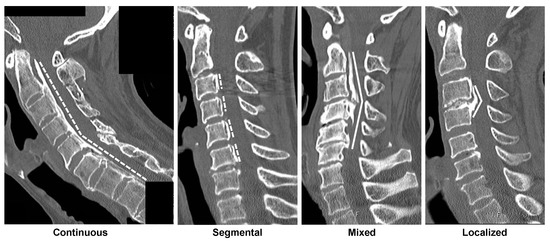

- Tetreault, L.; Nakashima, H.; Kato, S.; Kryshtalskyj, M.; Nagoshi, N.; Nouri, A.; Singh, A.; Fehlings, M.G. A systematic review of classification systems for cervical ossification of the posterior longitudinal ligament. Glob. Spine J. 2019, 9, 85–103. [Google Scholar] [CrossRef] [PubMed]